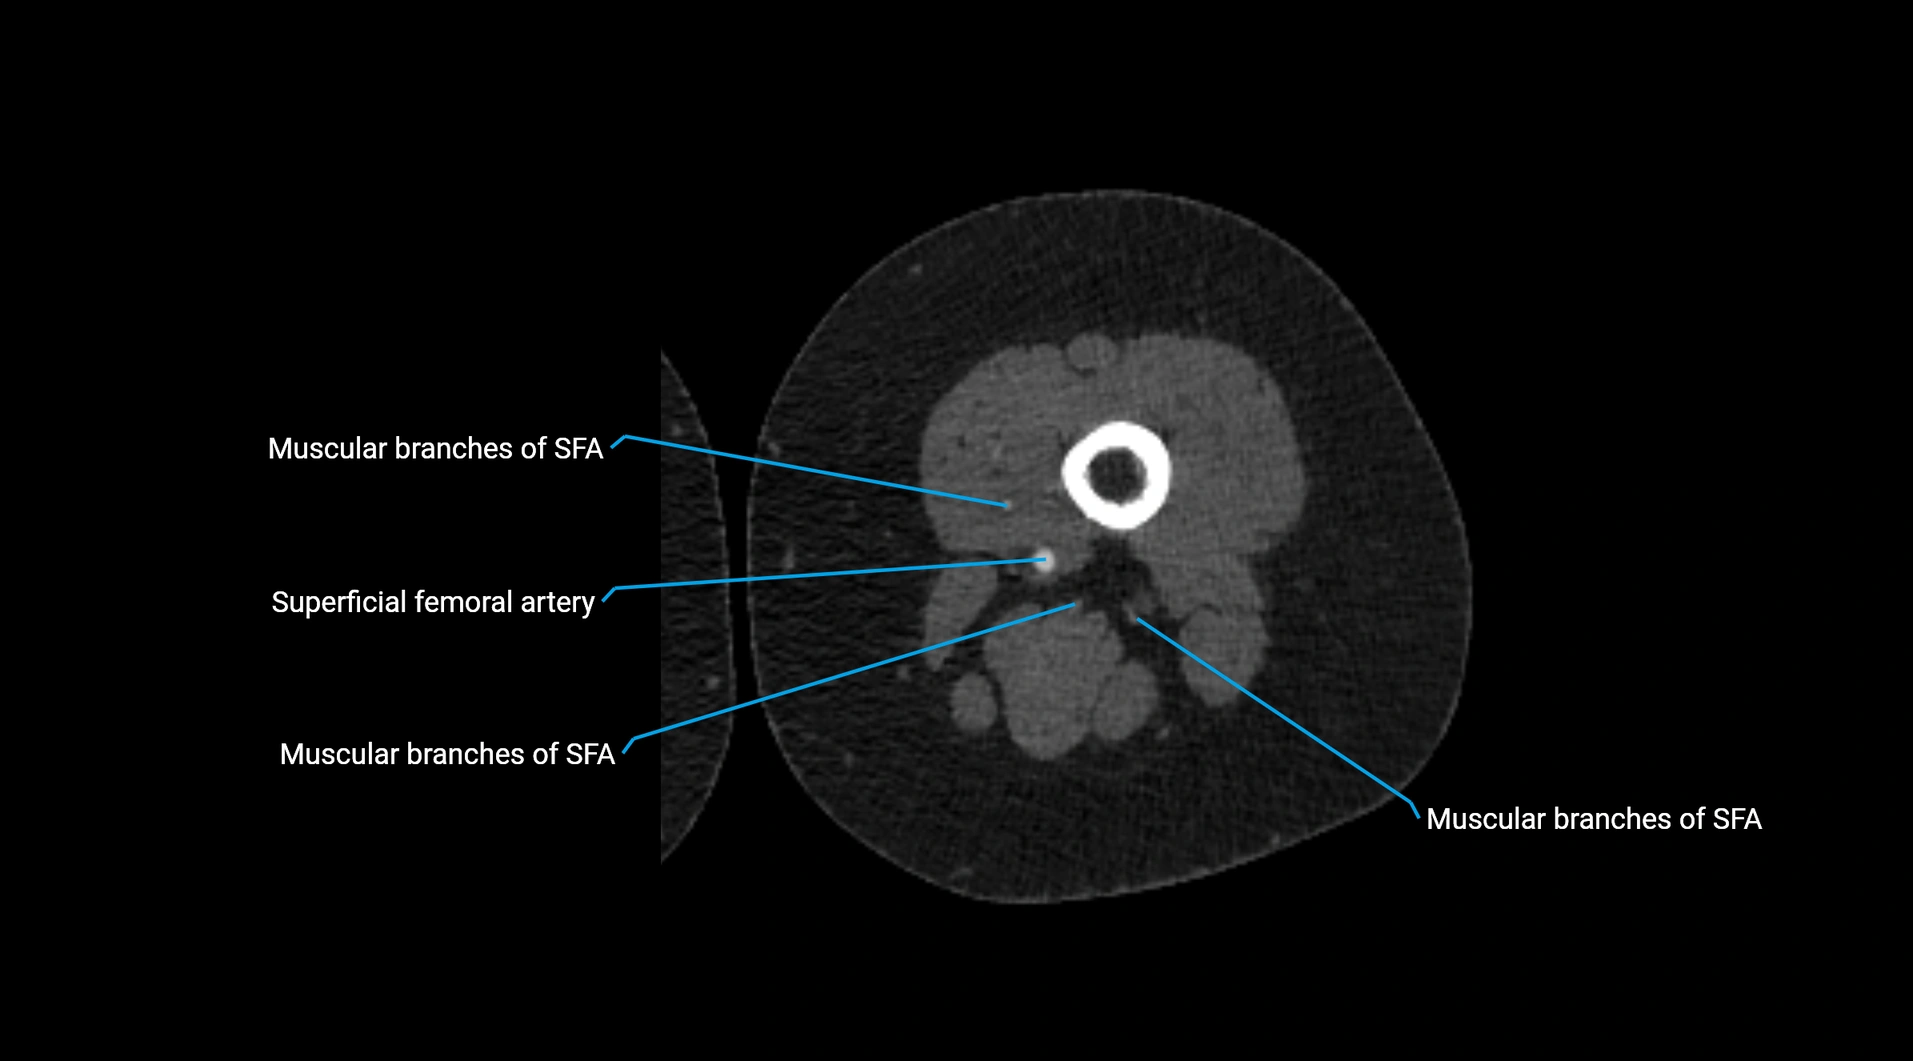

CT images

image

Contrast-enhanced CT (CTA):

• Gold standard for abdominal aortic imaging

• Provides excellent detail of lumen, wall, aneurysm, thrombus, and branch vessels

• Multiplanar and 3D reconstructions help in aneurysm measurement, stent graft planning, and dissection evaluation